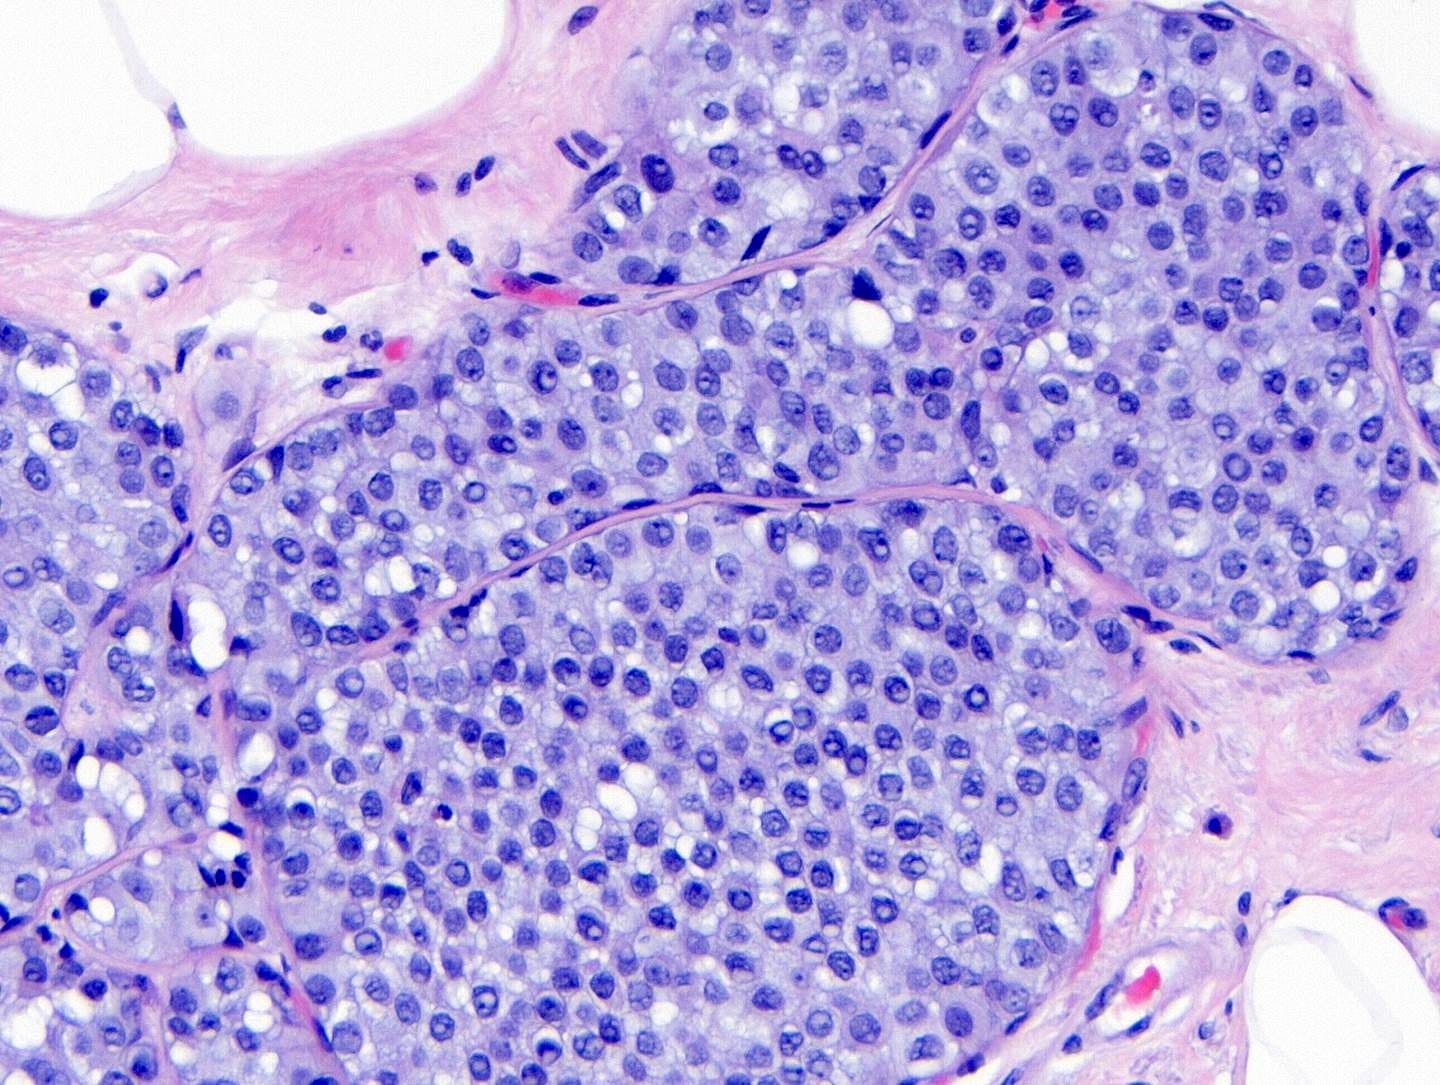

Classic LCIS - microscopic images

As shown below, LCIS is characterized by a lobulocentric proliferation of cells that expand lobular units. The LCIS cells are uniform, loosely cohesive and evenly spaced (“marbles in a bag”). They are slightly larger than normal breast epithelial cells, with indistinct cell borders and pale cytoplasm. Two types may coexist. Type A LCIS cells have small to slightly enlarged, uniform, round nuclei with inconspicuous nucleoli. Type B cells have larger nuclei, more abundant cytoplasm and more prominent nucleoli.

Classic LCIS is usually an incidental finding in a breast biopsy performed for other indications, including screening detected calcifications or mass producing lesions. The calcifications are frequently produced by columnar cell lesions, a low risk lesion. LCIS lesions are frequently found as multiple foci within the same (70%) or both breasts (20 - 60%).

LCIS is a risk factor for subsequent breast cancer: women with LCIS have a 7 - 10 fold increase in breast cancer risk, an absolute risk of 1 - 2% per year and a lifetime risk of 30 - 40%. The time from LCIS diagnosis to cancer ranges from 15 to 30 years.

Classic LCIS is typically treated conservatively with active surveillance and anti estrogens. Unlike DCIS, it is no longer considered a malignant condition. If diagnosed incidentally, excision is not recommended because the risk of finding invasive carcinoma on excision is very low (< 5%). Excision is recommended only if other high risk proliferative lesions are found or there is discordance between histology and imaging (i.e. the microscopic findings are different from what is expected from the imaging, suggesting the lesion was missed).